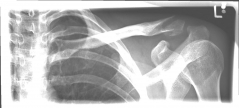

Picture 1: Displaced fracture of the left collarbone before surgery.